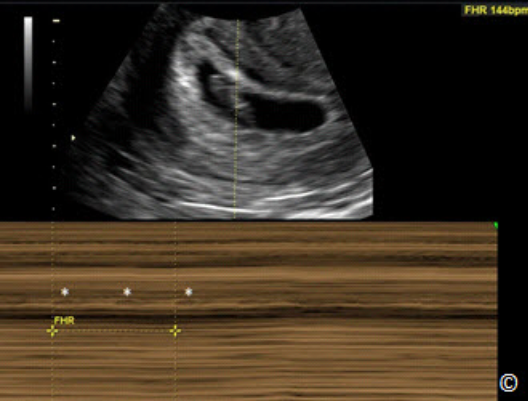

M-Mode: The M-Mode knob activates the M-Mode function of the ultrasound machine. MMode stands for Motion mode and in this function an M-Mode cursor line appears on the upper

section of the image with an M-Mode display on the lower part of the image (Figure 2.14). The

M-Mode display corresponds to the anatomic components that the M-Mode cursor intersects.

The M-Mode is used primarily to document motion, such as cardiac activity of the fetus in early

gestation (Figure 2.15).

Figure 2.15: M-Mode applied in the first trimester for documentation of fetal heart

activity. Reflections in the M-Mode tracing (asterisks) represent cardiac motion.

Calipers are measuring fetal heart rate (FHR) at 144 beats per minute (bpm).